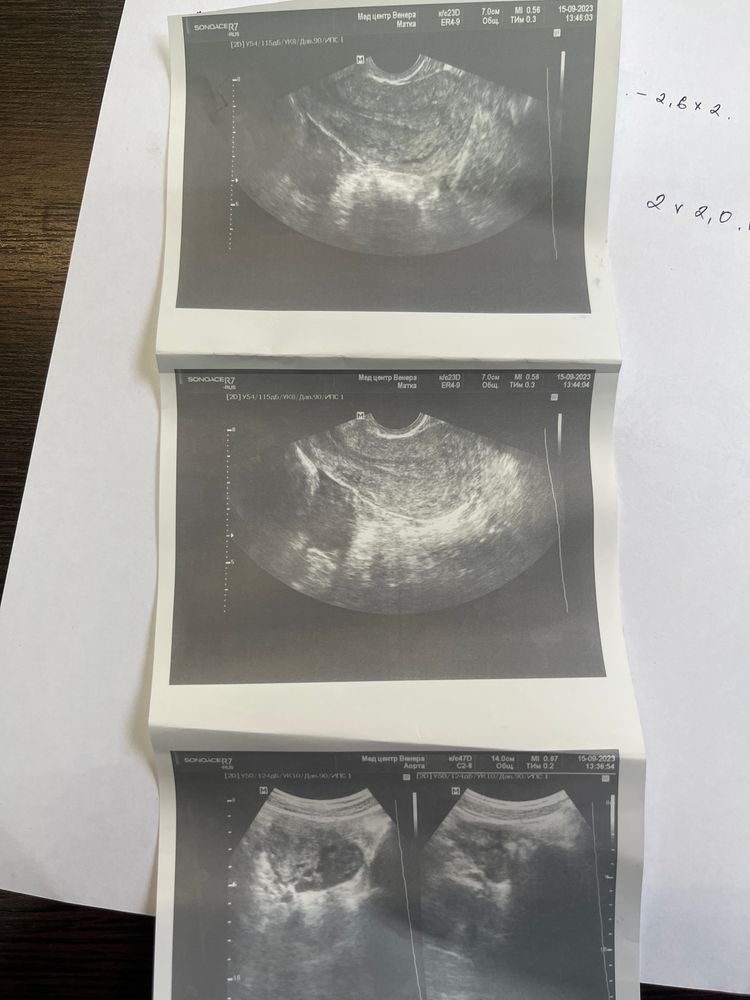

Mira, Изображение Изображение

Сделала узи для подтверждения 26 день цикла, я так понимаю овуляции не было , про желтое тело ничего не сказали, значит пролет?